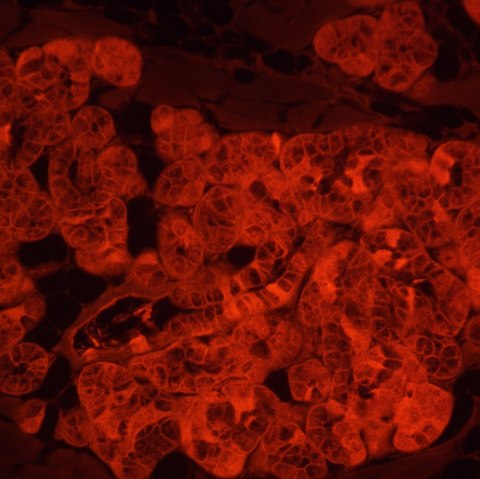

MAGUS Lum V500L to odwrócony mikroskop do mikroskopii fluorescencyjnej w świetle odbitym oraz mikroskopii jasnego pola i kontrastu fazowego w świetle przechodzącym. W mikroskopii fluorscencyjnej wykorzystywane są filtry fluorochromowe DAPI, FITC i TRITC. Odwrócona konstrukcja umożliwia badanie preparatów w naczyniach laboratoryjnych, takich jak szalki Petriego, kolby itp. Wysokość naczynia laboratoryjnego może wynosić 55 mm lub 165 mm, gdy stojak jest odchylony. Układ optyczny jest przeznaczony do pracy z naczyniami laboratoryjnymi o grubości dna 1,2 mm. Mikroskop jest idealny do badań naukowych i rutynowych prac laboratoryjnych. Można go również stosować do celów edukacyjnych.

MAGUS Lum V500L to odwrócony mikroskop do mikroskopii fluorescencyjnej w świetle odbitym oraz mikroskopii jasnego pola i kontrastu fazowego w świetle przechodzącym. W mikroskopii fluorscencyjnej wykorzystywane są filtry fluorochromowe DAPI, FITC i TRITC. Odwrócona konstrukcja umożliwia badanie preparatów w naczyniach laboratoryjnych, takich jak szalki Petriego, kolby itp. Wysokość naczynia laboratoryjnego może wynosić 55 mm lub 165 mm, gdy stojak jest odchylony. Układ optyczny jest przeznaczony do pracy z naczyniami laboratoryjnymi o grubości dna 1,2 mm. Mikroskop jest idealny do badań naukowych i rutynowych prac laboratoryjnych. Można go również stosować do celów edukacyjnych.

Źródłem wzbudzenia fluorescencji jest dioda LED o mocy 5 W i żywotności 50 000 godzin bez konieczności wymiany. Dostępne są trzy filtry wzbudzenia: filtry fluorochromowe DAPI, FITC i TRITC. Oświetlenie LED jest bardziej energooszczędne i łatwiejsze w utrzymaniu niż oświetlenie rtęciowe, dlatego jest zalecane do stosowania na uniwersytetach. Oświetlenie LED zapewnia spójność kolorów. Diody LED szybko włączają się i wyłączają i nie przegrzewają się podczas długich godzin pracy.

- Techniki obserwacji mikroskopowych: fluorescencja (w świetle odbitym), jasne pole i kontrast fazowy (w świetle przechodzącym)

| Moduł fluorescencyjny | Fluorochromy: DAPI, FITC, TRITC |

| Filtr fluorescencyjny: typ filtra, długość fali wzbudzenia/zwierciadło dichroiczne/długość fali emisji | DAPI, 365/35 nm/400 nm/450/65 nm; FITC, 475/40 nm/500 nm/535/45 nm; TRITC, 525/45 nm/565 nm/595/60 nm |

| Metoda badania | fluorescencja, jasnego pola, mikroskopia kontrastu fazowego |